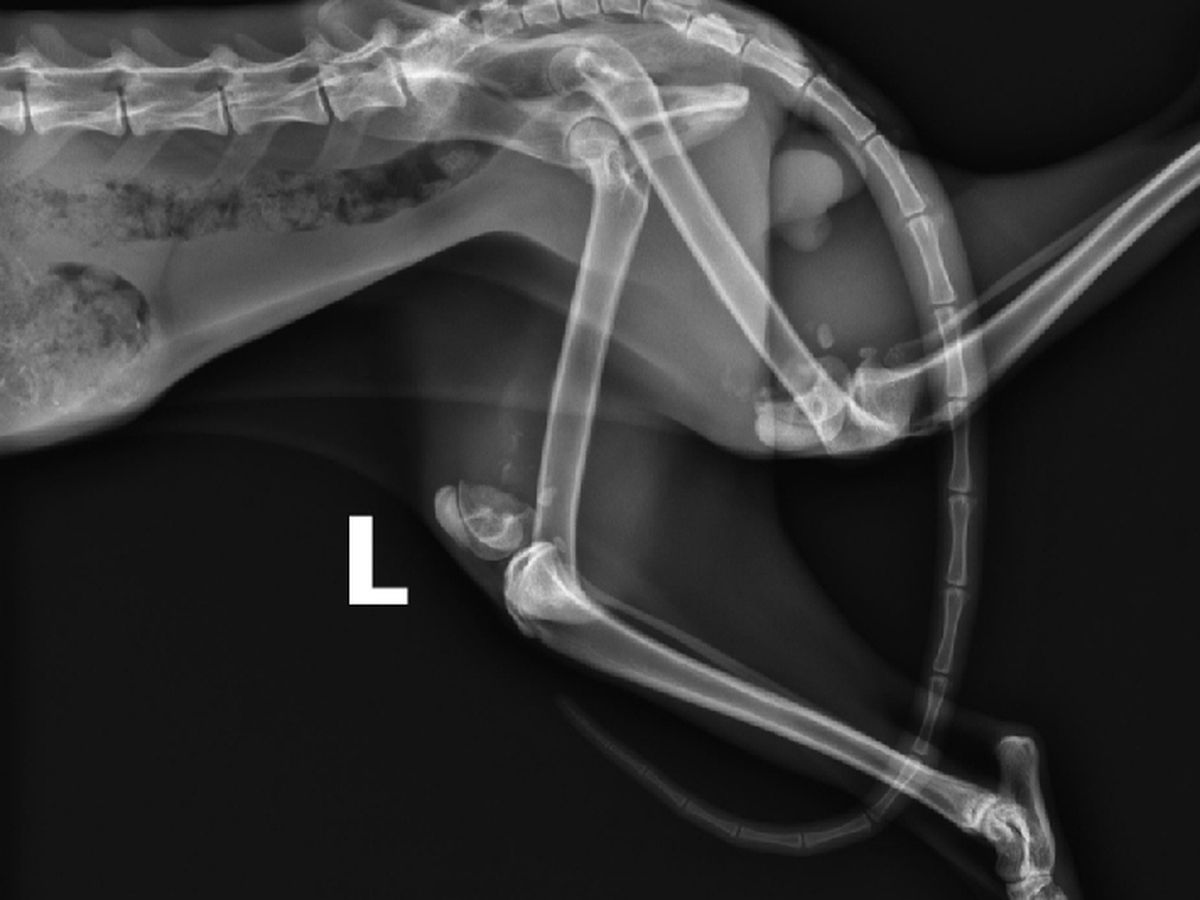

Simon is a one-year-old cat rescued from a neighbor's yard on July 19, 2021. Simon needs life-altering surgery to correct both of his back legs which were broken when he was younger and healed improperly because he didn't receive medial care.

- Two separate surgeries, one for each leg. Total cost 9/29/21 Update: $5400 ($2700 per leg)

- Smooth the top part of the lower bone that sticks out on the inside of his legs. (updated 9/29/21)

- Attach the two parts with a metal plate & screws - As of 9/29/21, we are no longer doing this.

A visit to the vet revealed the problem. Both back legs had been broken at some point and didn’t heal properly because the kitty never received medical help. The vet said it would require a specialist surgeon to correct the problem and it would be expensive. While this was sad to hear, at least kitty was in not in need of critical care like we feared. Even though he was clearly emaciated, he weighed 8 pounds. Blood tests showed him to be FIV+. He got his vaccines and rabies shot.

On August 16, Simon had his consultation with the surgeon. After discussion of options and risks, we scheduled the first surgery for 8/24. Estimated cost per leg is $4000. Cost updated to $2700 per leg as of 9/29/21.